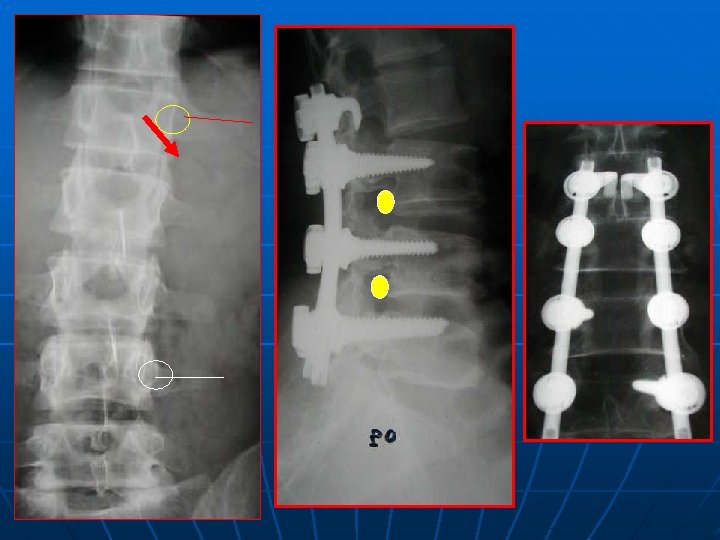

SPONDYLOLESTHESIS ISTHMIQUE Rx standard: face+profil+3/4 D-G Découverte au stade de déplacement n Lombalgies isolées: pas d’autres explorations n Lombosciatiques: Rx dynamiques+ grand format+IRM ( TDM peu d’apport) n

CLASSIFICATION DE MYEREDING

52 ans, spondylo L 5 -S 1 grade I, Beaujon 10

+18 mois, Beaujon 80%

CONCLUSION n n LOMBALGIES ISOLEE: Rx standard RADICULALGIES: Rx dynamiques, grand format, IRM: étude du disque sus jacent pour l’étendue de l’arthrodèse